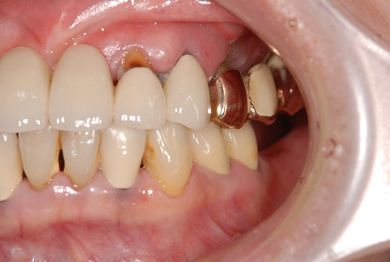

インプラントの症例写真 IMPLANT

| 性別/年齢 | 女性 / 58歳 | ||||||||||||||||||||||||||||||||

| 主訴 | インプラント治療を希望。 | ||||||||||||||||||||||||||||||||

| 治療内容 | インプラント8本(抜歯即日スピードインプラント、サイナスリフト)、ハイブリッドセラミック8本 | ||||||||||||||||||||||||||||||||

| 総治療費 | 3,495,050円 | ||||||||||||||||||||||||||||||||

| 治療期間 | 1年0ヶ月 |